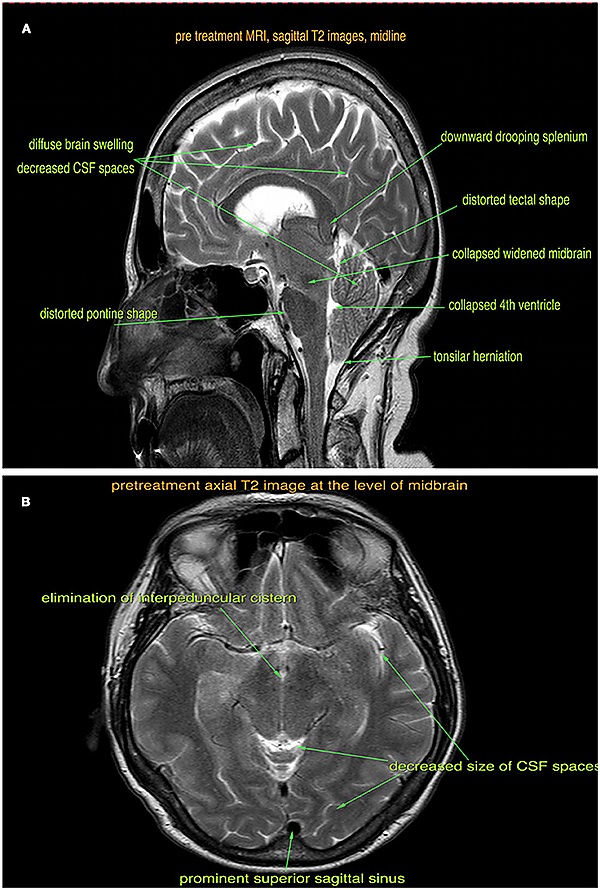

Магнитно-резонансная томография. В ходе исследования выявляют утолщение мозговых оболочек, опущение миндалин мозжечка в большое затылочное отверстие, скопление ликвора в субдуральном пространстве головного мозга, увеличение размеров гипофиза, мамиллопонтинное расстояние менее 5,5 мм и понтомезенцефалический угол менее 50 °[3], каллозальный угол менее 90 °[6].